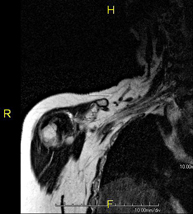

- RM d'Espatlla

Exploració per a l'estudi de lesions en els tendons, els músculs i les articulacions. La seva principal utilitat resideix en diagnosticar les lesions dels tendons del braçal rotatori. Té una durada aproximada de 20 minuts. No utilitza radiació ionitzant. - RM de Braç